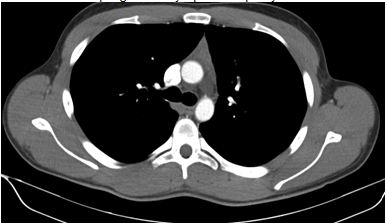

An abnormality was noted in the left mediastinum which prompted his physician to order a computed tomography (CT) of the chest and to refer him to a pulmonary specialist. This CT scan (Figures 2 and 3) revealed a rounded, well-demarcated mass in the superoanterior mediastinal compartment. The largest diameter measured 6.8 x 4.8cm.

Figure 2. Computed tomography (CT) image of the chest demonstrating well-demarcated soft tissue mass in superoanterior mediastinal mass (arrow).

Figure 3. Computed tomography (CT) image of the chest demonstrating well-demarcated soft tissue mass in superoanterior mediastinal mass (arrow).